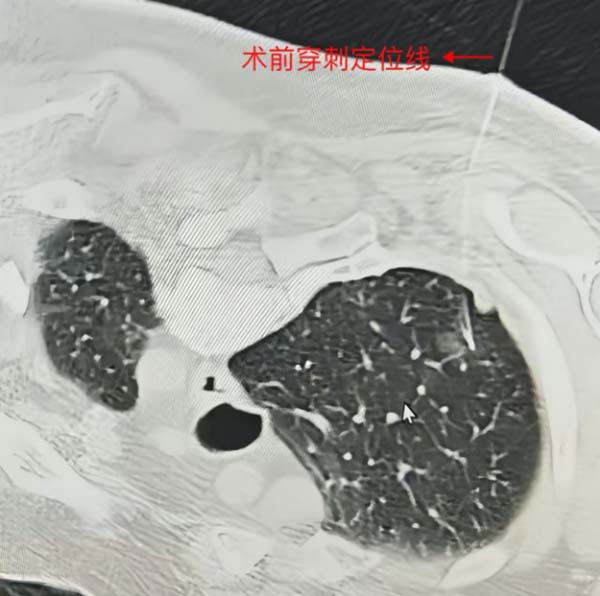

图2 术前穿刺定位线

李女士的结节在3年内从5mm增长至10mm,属于典型的“有临床意义的生长”,手术指征明确。患者入院后,我院外科胸外组团队进行了详细术前评估:(1)肺功能检测:耐受良好;(2)薄层CT三维重建:精准定位结节位置、形态及与周围血管的关系;(3)肿瘤标志物:无异常升高。经过综合研判,团队决定实施胸腔镜右肺上叶楔形切除术——仅需一个约3cm的操作孔,完成结节的精准切除。